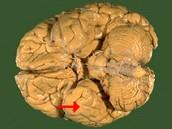

如图箭头所示为大脑哪个部位 ( )A、顶叶B、岛叶C、颞叶D、枕叶E、额叶一、单项选择题

问题 如图箭头所示为大脑哪个部位 ( )

选项 A、顶叶 B、岛叶 C、颞叶 D、枕叶 E、额叶 一、单项选择题

答案 C